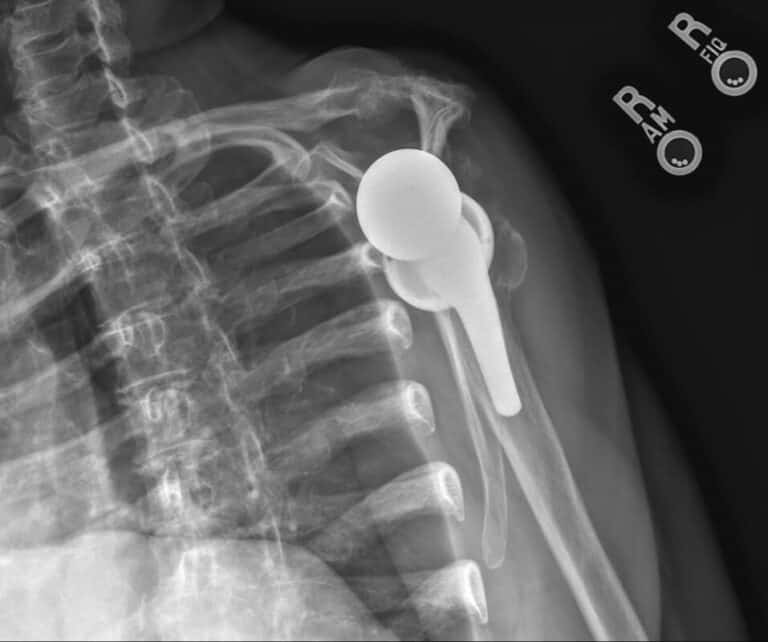

Stryker/Wright/Tornier, Flex Ascend Humerus, Perform Half Wedge Glenoid